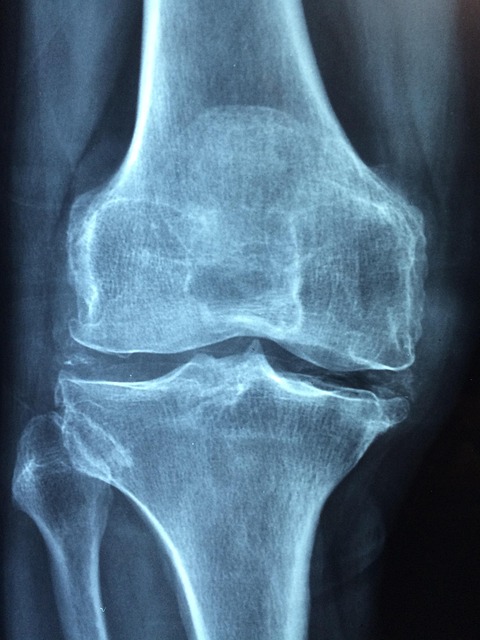

콘드로이친은 관절 연골의 주요 구성 성분으로, 골관절염 증상 완화에 도움을 주는 건강 보조제입니다. 임상 연구를 기반으로 한 정확한 콘드로이친 복용법을 알아보겠습니다.

- 경증~중등도 골관절염: 800mg/일 (1회 복용)

- 중등도~중증 골관절염: 1,000–1,200mg/일 (2–3회 나누어 복용)